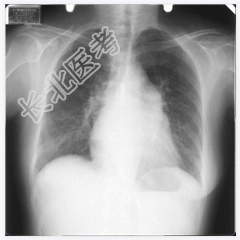

- [材料题] 女,50岁,主诉:胸闷、心悸4个月。听诊:心尖部听到舒张期和收缩期杂音。

- 简答题1、请问该案例诊断是什么?

- 简答题2、请问诊断依据是什么?